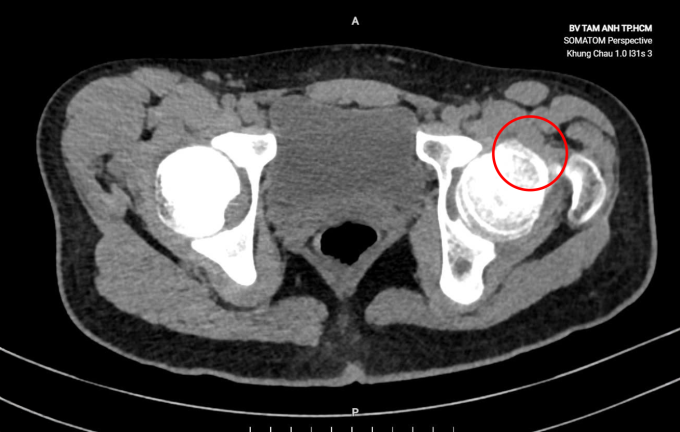

Kết quả siêu âm và chụp CT tại Bệnh viện Đa khoa Tâm Anh TP HCM ghi nhận khớp háng của Phát xuất hiện một mô xương bất thường, nhô cao, kích thước khoảng 5x10 mm chiếm gần hết diện tích phía trước của chỏm xương đùi. ThS.BS.CKI Nguyễn Xuân Trường, Trung tâm Chấn thương Chỉnh hình, chẩn đoán thiếu niên này mắc hội chứng cấn khớp háng - một bệnh lý ít gặp. Tình trạng này xảy ra khi xương hông phát triển bất thường không rõ nguyên do, làm xuất hiện một mảng xương nhô cao hơn ở chỏm xương đùi.